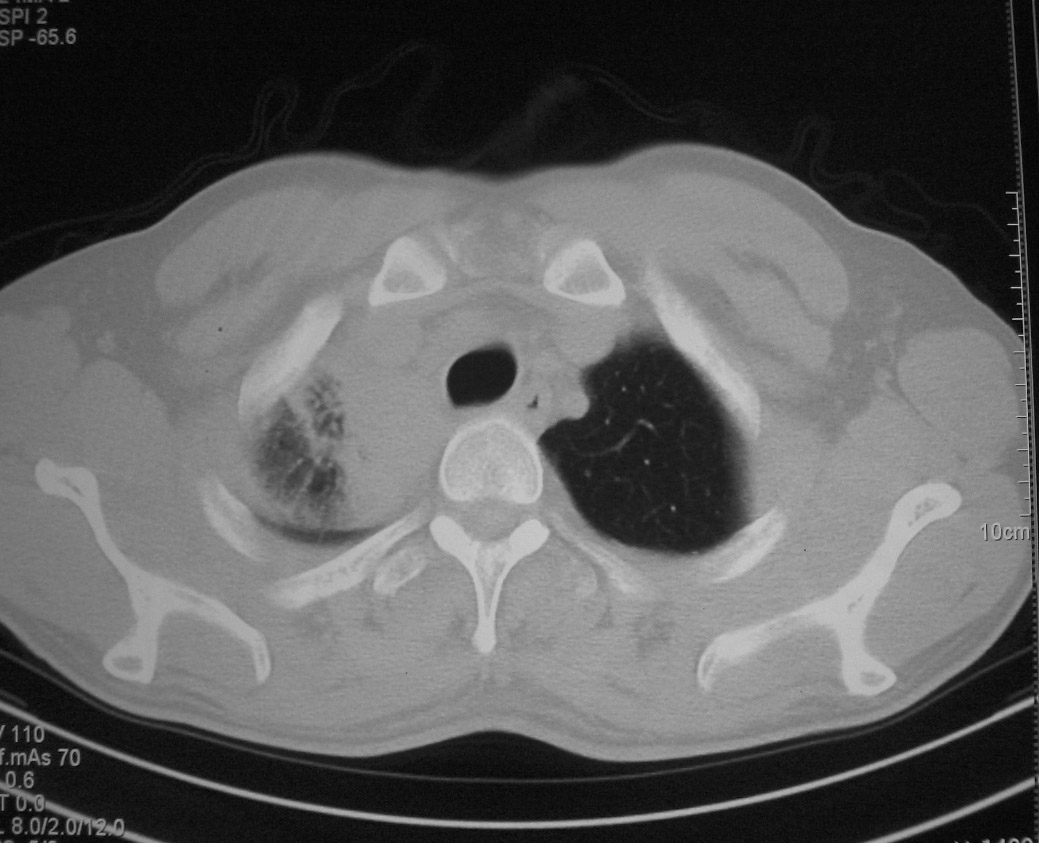

标题: CT5485:[原创]肺部占位请讨论

右肺上叶中央型肺癌并上叶肺不张、纵隔淋巴结肿大

右上叶支气管后壁明显增厚,支持右肺上叶中央型肺癌伴右上叶肺不张、纵隔淋巴结肿大。

右上叶支气管后壁明显增厚,支持右肺上叶中央型肺癌伴右上叶肺不张、纵隔淋巴结肿大。建议支气管镜检查。

右上叶支气管开口变窄,纵隔见肿大的淋巴结。支持右上叶中心型肺癌并右上叶不张纵隔淋巴结肿大。

右肺上叶中央型肺癌并上叶肺不张、纵隔淋巴结肿大.右侧少量胸腔积液。

右肺上叶支气管后壁增厚,呈鼠尾状狭窄,纵隔内未见明显增大的淋巴结影,考虑为中央型肺癌伴右上肺不张

右肺上叶不张,考虑中央型肺癌。右侧胸膜肥厚

右肺上叶中央型肺癌并阻塞性炎症、阻塞性肺不张……